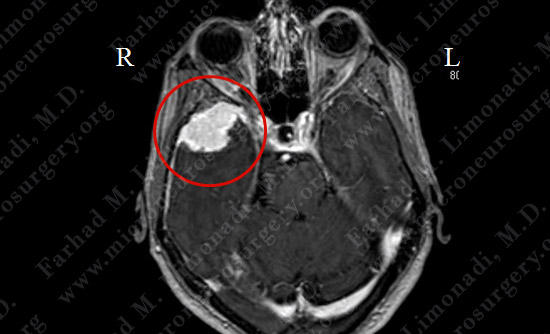

MRI scan of the patient's brain showed a dural-based temporal tumor on the right side.